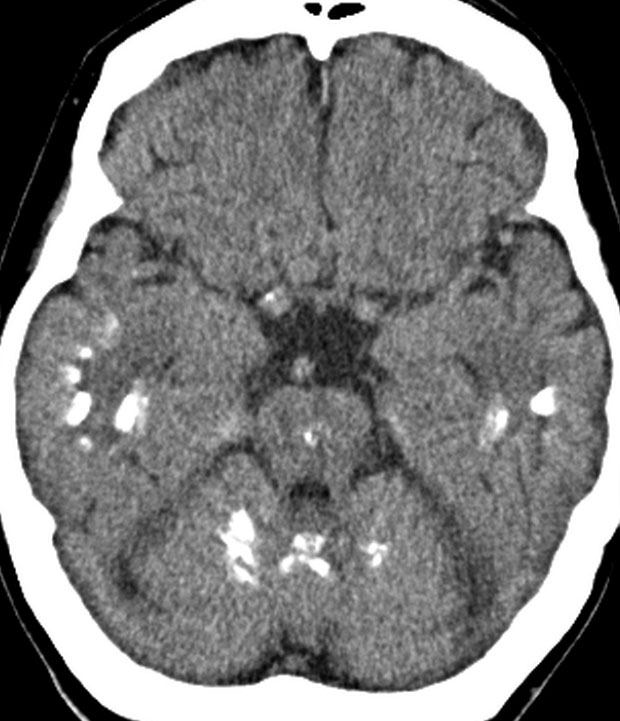

全脳照射後の脳内石灰化(幼児例)

20年以上前のことですが,髄芽腫の1歳6ヶ月の子どもに25グレイの全脳照射をしました。これは15年後のCTです。

脳の萎縮は目立ちません。認知機能は低いのですが支援を受けて学校へ行けています。下垂体機能は低下して成長ホルモンなどの補充をして普通に暮らせています。

CTで,両側の大脳基底核(被殻と淡蒼球)と視床後部に石灰化がみられます。乳幼児期に放射線治療を受けた子どもに見られるものです。